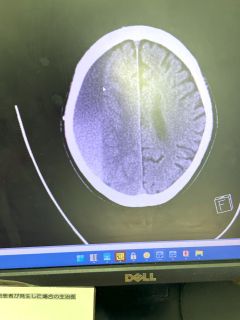

その間の検査の結果、15時脳の異常が発見される。

慢性硬膜下血腫とのこと。

明日の午後1時以降で手術とのこと。